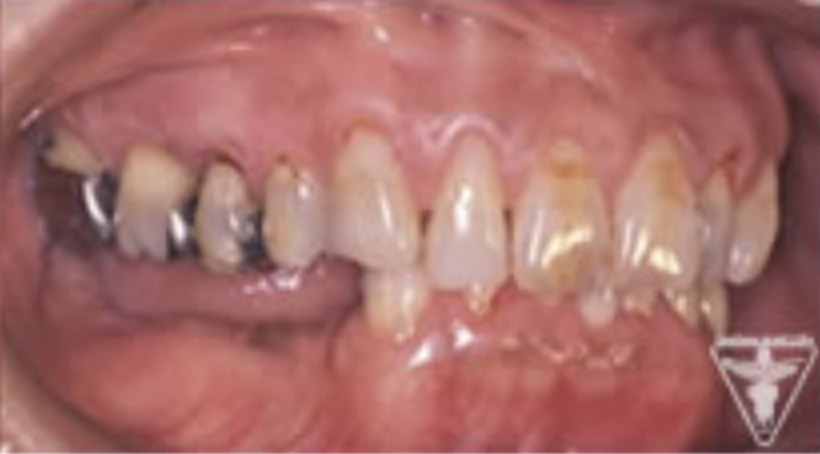

治療前

下の奥歯が左右なくなっており、かみ合わせが深くなっています。

顎のずれは認めませんが、歯肉が厚く中に炎症を取りこみやすいタイプの歯肉です。

左の顎の骨が大きく溶けてなくなっております。